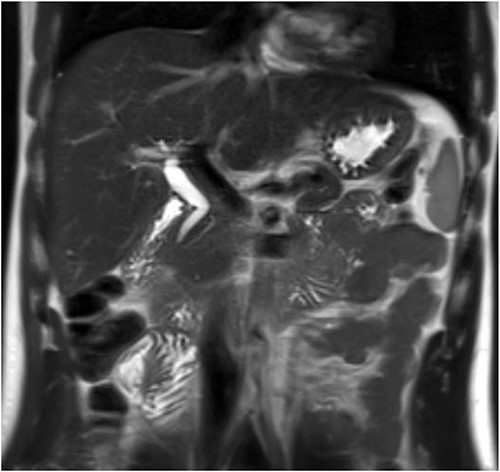

The patient was discharged home on recovery and planned for outpatient MRCP and repeat LFTs. MRCP showed no gallbladder or cystic duct identified consistent with congenital agenesis (Figs 3 and 4). CBD was mildly dilated to 9 mm but tapers appropriately to the ampulla with no evidence of biliary stricture or choledocholithiasis. The repeat LFTs were normal.

Post-operative MRCP confirming congenital gallbladder agenesis.